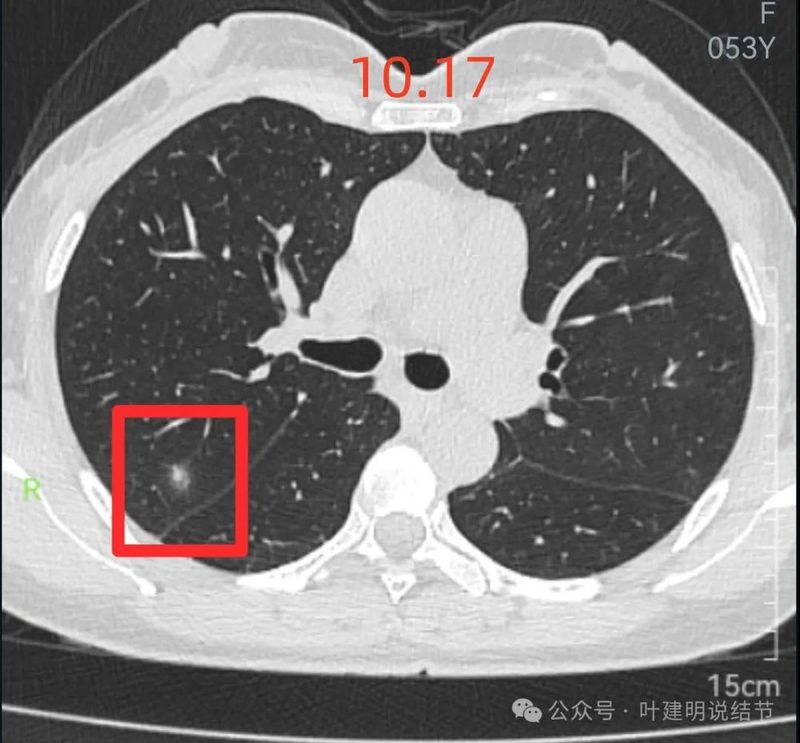

12月17号复查胸部CT,10月17号发现的混杂毛玻璃结节消失了,烦请叶主任诊断12月17号报告上结节的现状,很佩服叶主任,现在不乱挂号了,直奔叶主任来,业务精湛,诊断清晰明了,是有大爱的医者。

前次问诊时上海某大医院教授认为必是恶性的病灶。

前次问诊时结友想知道复查申请何种CT,我告诉她无所谓的,反正到时候病灶基本就吸收了。

结友在我针对她的问诊进行分析的文章后方留言,告诉大家病灶已经完全吸收。

原来病灶处已经几乎不见异常。